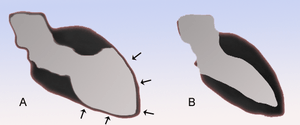

| Schematic representation of takotsubo cardiomyopathy (A) compared to a normal heart (B). | |

Takotsubo cardiomyopathy, also known as stress cardiomyopathy, is a type of non-ischemic cardiomyopathy in which there is a sudden temporary weakening of the muscular portion of the heart.[3] This weakening can be triggered by emotional stress, such as the death of a loved one, a break-up, or constant anxiety.[4] Stress cardiomyopathy is now a well-recognized cause of acute heart failure, lethal ventricular arrhythmias, and ventricular rupture.[5]

The name "takotsubo syndrome" comes from the Japanese word for a kind of octopus trap (ja),[5] because the left ventricle takes on a shape like a fishing pot.

The typical presentation of takotsubo cardiomyopathy is a sudden onset of chest pain associated with ECG changes mimicking a myocardial infarction of the anterior wall. During the course of evaluation of the patient, a bulging out of the left ventricular apex with a hypercontractile base of the left ventricle is often noted. It is the hallmark bulging out of the apex of the heart with preserved function of the base that earned the syndrome its name "tako tsubo", or octopus pot in Japan, where it was first described.[6]